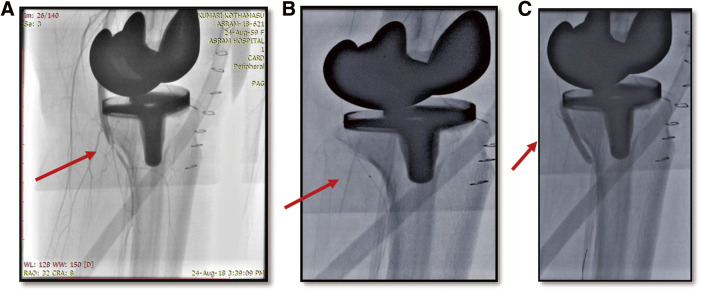

目的:本研究的目的是探讨全膝关节置换术(TKA)后腘动脉血栓形成导致急性肢体缺血(ALI)的罕见并发症的发生、临床特征、治疗方法和结果。方法:对1020例TKA手术进行回顾性研究。通过临床评估和动脉多普勒检查确定ALI病例。周围血管成形术使腘动脉再通。评估其表现、并发症及处理策略。结果:1020例TKA中,ALI 5例,占全部TKA病例的0.49%。女性优势和左侧表现是值得注意的观察结果。大多数患者在8小时内出现症状,伴有足部下垂到筋膜室综合征等多种并发症。除1例外,其余患者均经吸血栓及球囊扩张后恢复。结论:TKA的腘动脉血栓形成是一种罕见但可能致命的并发症,因此早期识别和干预以减轻不良后果非常重要。在我们的研究中,就有效管理和减少手术并发症和发病率而言,血管内治疗已成为首选方式。

Objectives: The objective of this research was to examine the occurrence, clinical features, treatment approaches, and results associated with a rare complication of thrombosis of the popliteal artery after total knee arthroplasty (TKA), leading to acute limb ischemia (ALI). Methods: A retrospective study on 1020 TKA procedures spanning 5 years. Cases of ALI were identified through clinical evaluation and arterial Doppler studies. Peripheral angioplasty was done to recanalize the popliteal artery. Manifestations, complications, and management strategies were evaluated. Results: Among the 1020 TKA cases, 5 cases of ALI were identified which accounts for 0.49% of all TKA cases. Female predominance and left-sided presentations are notable observations. Most patients presented within 8 hours of symptom onset with diverse complications ranging from foot drop to compartment syndrome. Except for 1 case, all patients recovered with thrombosuction and balloon dilatation. Conclusions: A rare but potentially fatal complication of TKA is popliteal artery thrombosis leading to ALI so it becomes important for early recognition and intervention to mitigate the adverse outcomes. In our study, endovascular treatment has emerged as the preferred modality in terms of effective management and reducing complications and morbidity from surgical procedures.